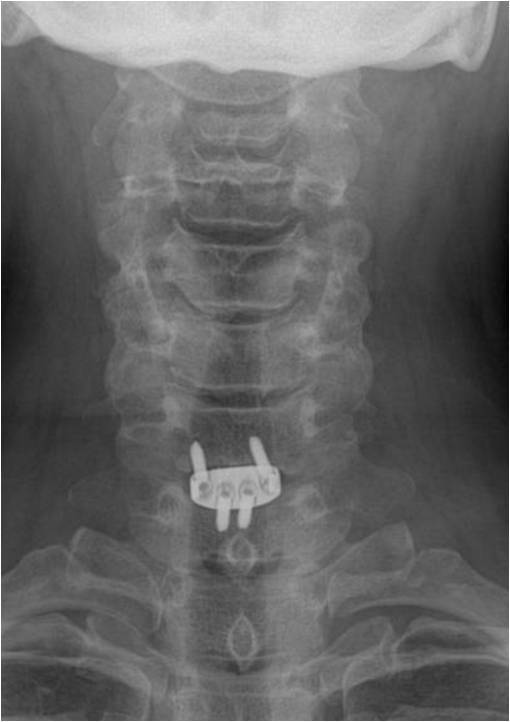

颈椎病产生的病理因素是椎间盘,无论是神经根型、还是脊髓型颈椎病。因椎间盘退变可导致脊髓、神经根等受压,亦可形成后方骨赘。那么处理该问题时,就不应该切除椎体,而应该以针对性椎间隙减压即可。所以,张教授在行颈前路手术时,均以单间隙减压充分为目的。无一例行椎体次全切手术。他强调:如有可能,尽量进行单节段固定、融合,强调零切迹的Zero-P的使用。这样,稳定程度高。

Zero-P融合固定 |

常规开展,最为推崇 |

省内率先开展(包括腰椎),医保、费用限制 |